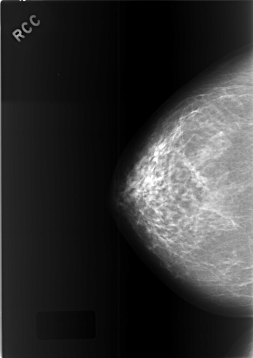

C_0449_1.RIGHT_CC

RIGHT_CC LINES 5728 PIXELS_PER_LINE 4048 BITS_PER_PIXEL 12 RESOLUTION 50 NON_OVERLAY